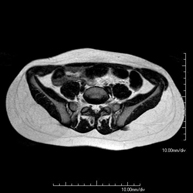

- RM Sacroilíacas

Prueba diagnóstica no invasiva que consiste en la obtención de imágenes de alta definición anatómica de las articulaciones sacroilíacas mediante el empleo de un campo electromagnético y ondas de radio (con un emisor y un receptor). No utiliza radiación ionizante. Indicaciones: dolor sacroilíaco inflamatorio. - RM ATM (Articulación Temporo-Mandibular)

Exploración para el estudio de lesiones en tendones, músculos y articulaciones coxofemorales. Permite identificar de forma precoz la artrosis de cadera. Resulta muy útil para detectar las bursitis y la osteopatía dinámica del pubis, frecuente en deportistas. Tiene una duración aproximada de 20 minutos. No emplea radiación ionizante. - RM Sacroilíacas

Estudio específicamente diseñado para valorar estas articulaciones y su inflamación en los pacientes que sufren Espondilitis Anquilosante. También resulta de utilidad en pacientes con traumatismos y posibles fracturas del sacro y el cóccix. Tiene una duración aproximada de 16 minutos. No emplea radiación ionizante. - RM Glúteos